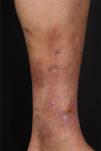

At the examination, she had well-defined achromic maculae, compatible with Milian’s white atrophy and erythematous maculae, in addition to an ulcer measuring 1.5 cm in diameter, with well-defined and erythematous edges with a fibrinous bottom, on the medial aspect of the left lower limb (Fig. 1).

Three short cycles of prednisone (0.5 mg/kg/day) were administered and 50 mg/day of dapsone was started, gradually increasing the dose to 150 mg/day. However, the patient developed spontaneous ulcers in the lower limbs. Dapsone was discontinued and azathioprine 100 mg/day was introduced, in addition to 20 mg/day of prednisone and maintenance of local care, with ulcer healing and pain relief in one month. After 5 months of follow-up, new lesions appeared, and an increase in the dose of azathioprine to 250 mg was prescribed, finally showing a good clinical response (Fig. 6).